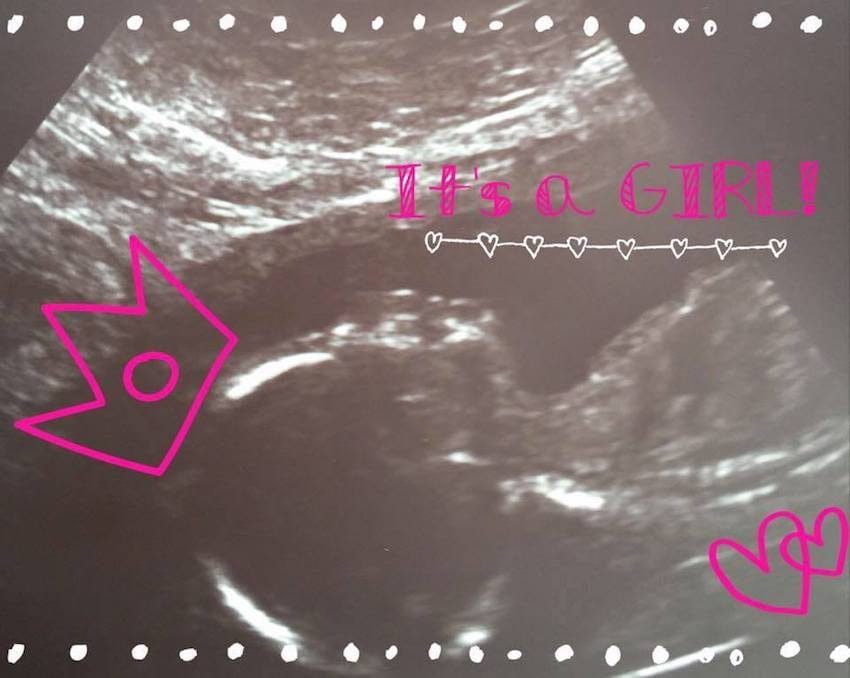

醫生告知他們可以在懷孕17周時觀察膀胱,當時他們確認了膀胱還在正確的位置,代表它沒有外翻。不過隨著時間過去,在21週時,他們再次觀察了寶寶的膀胱,並做好最壞的打算,「就算醫生告訴我們寶寶膀胱外翻了,我們也會說:『好,知道了』。」

▼「我永遠不會忘記2017年1月10日,那一天我26歲,懷孕21週,」艾蜜莉說,「超聲波的技術物人員把儀器滑到我肚子上,我們的醫生告訴她:『在那裡,停下來!』」艾蜜莉瞬間被安心感淹沒了,他們看到了寶寶的膀胱依然在體內,代表他沒有外翻,沒有任何疾病!